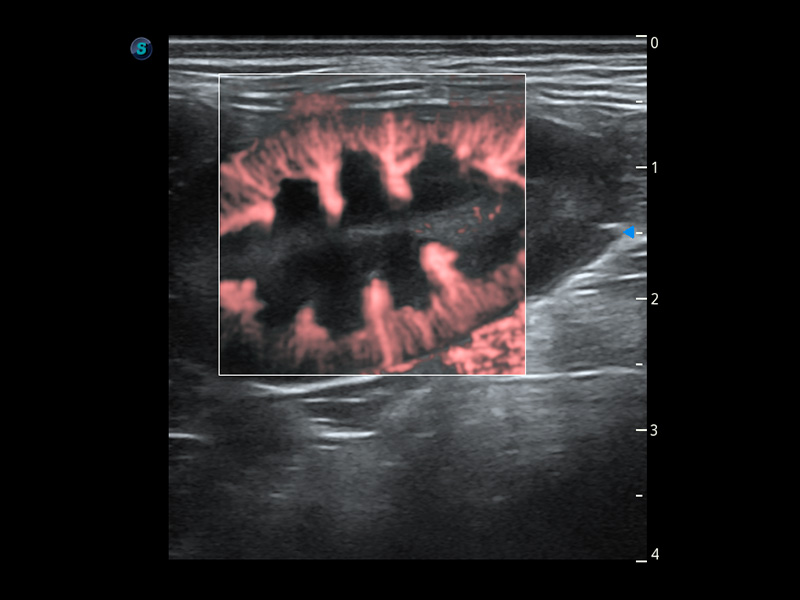

4T血流成像 微察秋毫

融合不同血流成像技术的优势,即可以提升血流成束性,同时可提高血流的视觉敏感性。

PDI 能量多普勒血流

提供高灵敏度和空间分辦率的血流图像,获得更加真实和丰富的诊断信息。

SR Flow 高分辨率血流成像

能够清晰显示细小、低速血流图像,获取传统彩色多普勒技术难以得到的细节和信息。

Micro F 显微血流成像

通过创新的Matrix E自适应滤波器和超长时间域算法,极大提升超低速微细血流的检出能力,同时更精准地滤除软组织和噪声信号,为兽用医生提供以往无法通过常规血流获得的疾病诊断信息。

Bright Flow 立体血流成像

在传统二维血流成像的基础上,呈现血流的立体感,具有动感的生命力之美。精确区分不同血管的空间关系,提高了血流的视觉敏感性。

优异的基础图像

(犬)四腔心血流

(犬)肾脏血流